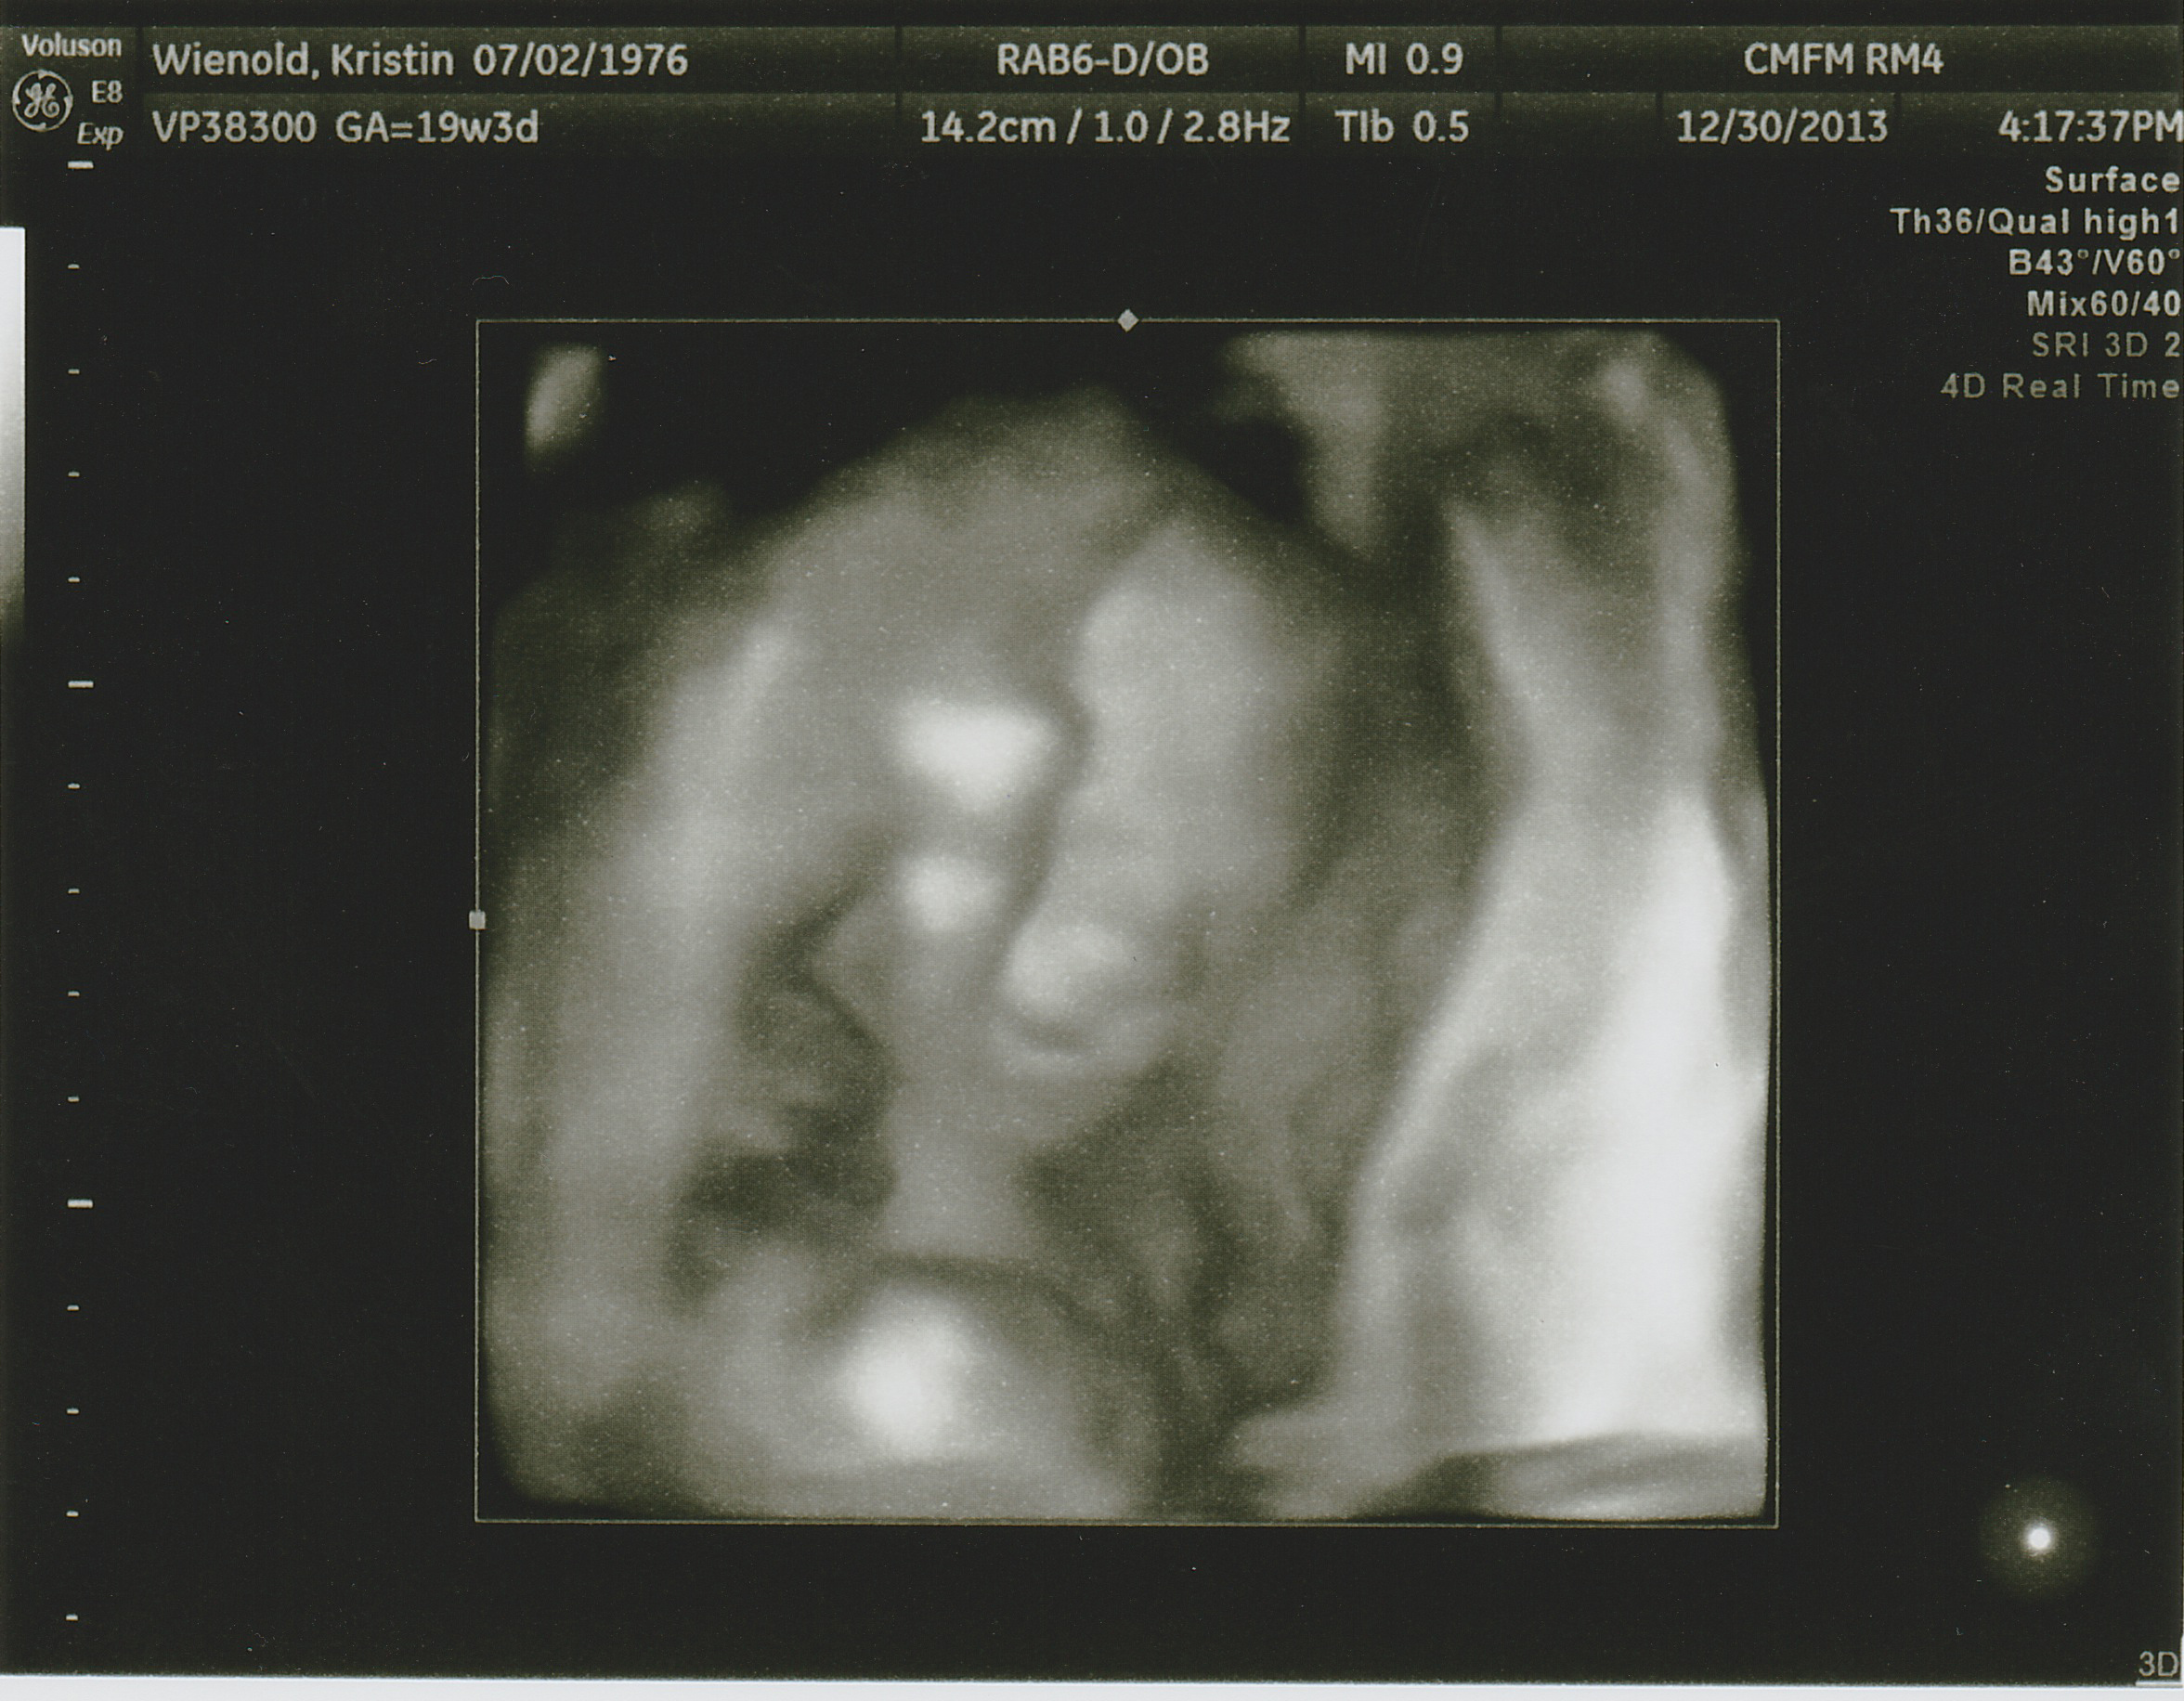

Yep… There’s a baby in there. “JP” as we call him will be here May 21st of 2014 and we simply could not be more excited. One of the constant questions we have gotten throughout the pregnancy is have you chosen a name yet? Well yes, we have… But we’re not going to tell you. Most folks are not that surprised with this response, except of course for Kris’ mom. It drives her crazy not to know. Out of this world bat-shit crazy. So J for John, P for Paul, the grandpas to be, was the suggestion by Lois. John-Paul, being rather papal, is about as likely as naming him Tire Iron or Cash Register, so its been fun to play along and tease dear grandma to be… That she will know as soon as everybody else does, what JPs real name is.